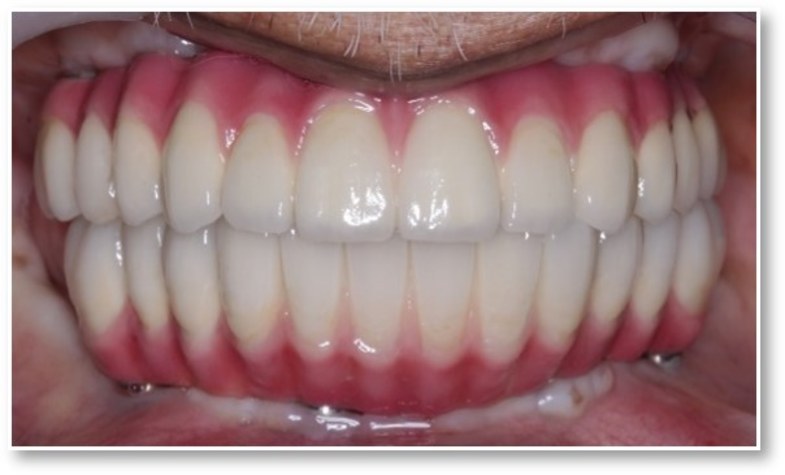

Full Mouth Rehabilitation

Complete reconstruction

Comprehensive restoration combining implants, crowns, and bridges to rebuild a full functional bite and natural-looking smile.